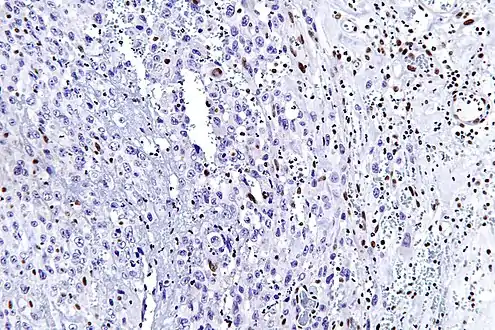

Intermed. mag.

High mag. (SMARCB1)